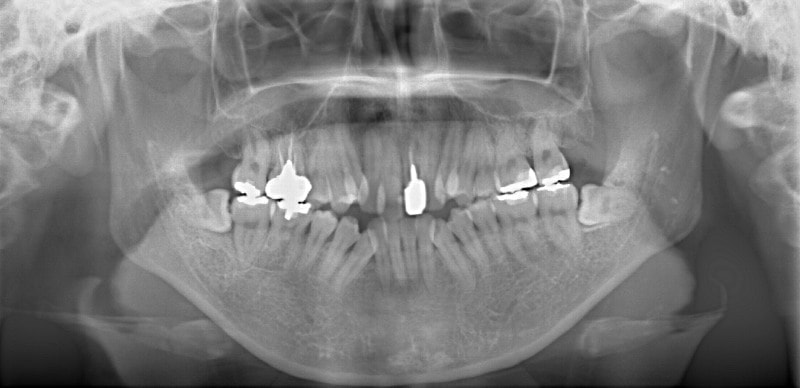

治療開始時

修復歯、補綴歯もあります。下顎8番が水平埋伏しています。

下顎8番は、両側抜歯済みです。